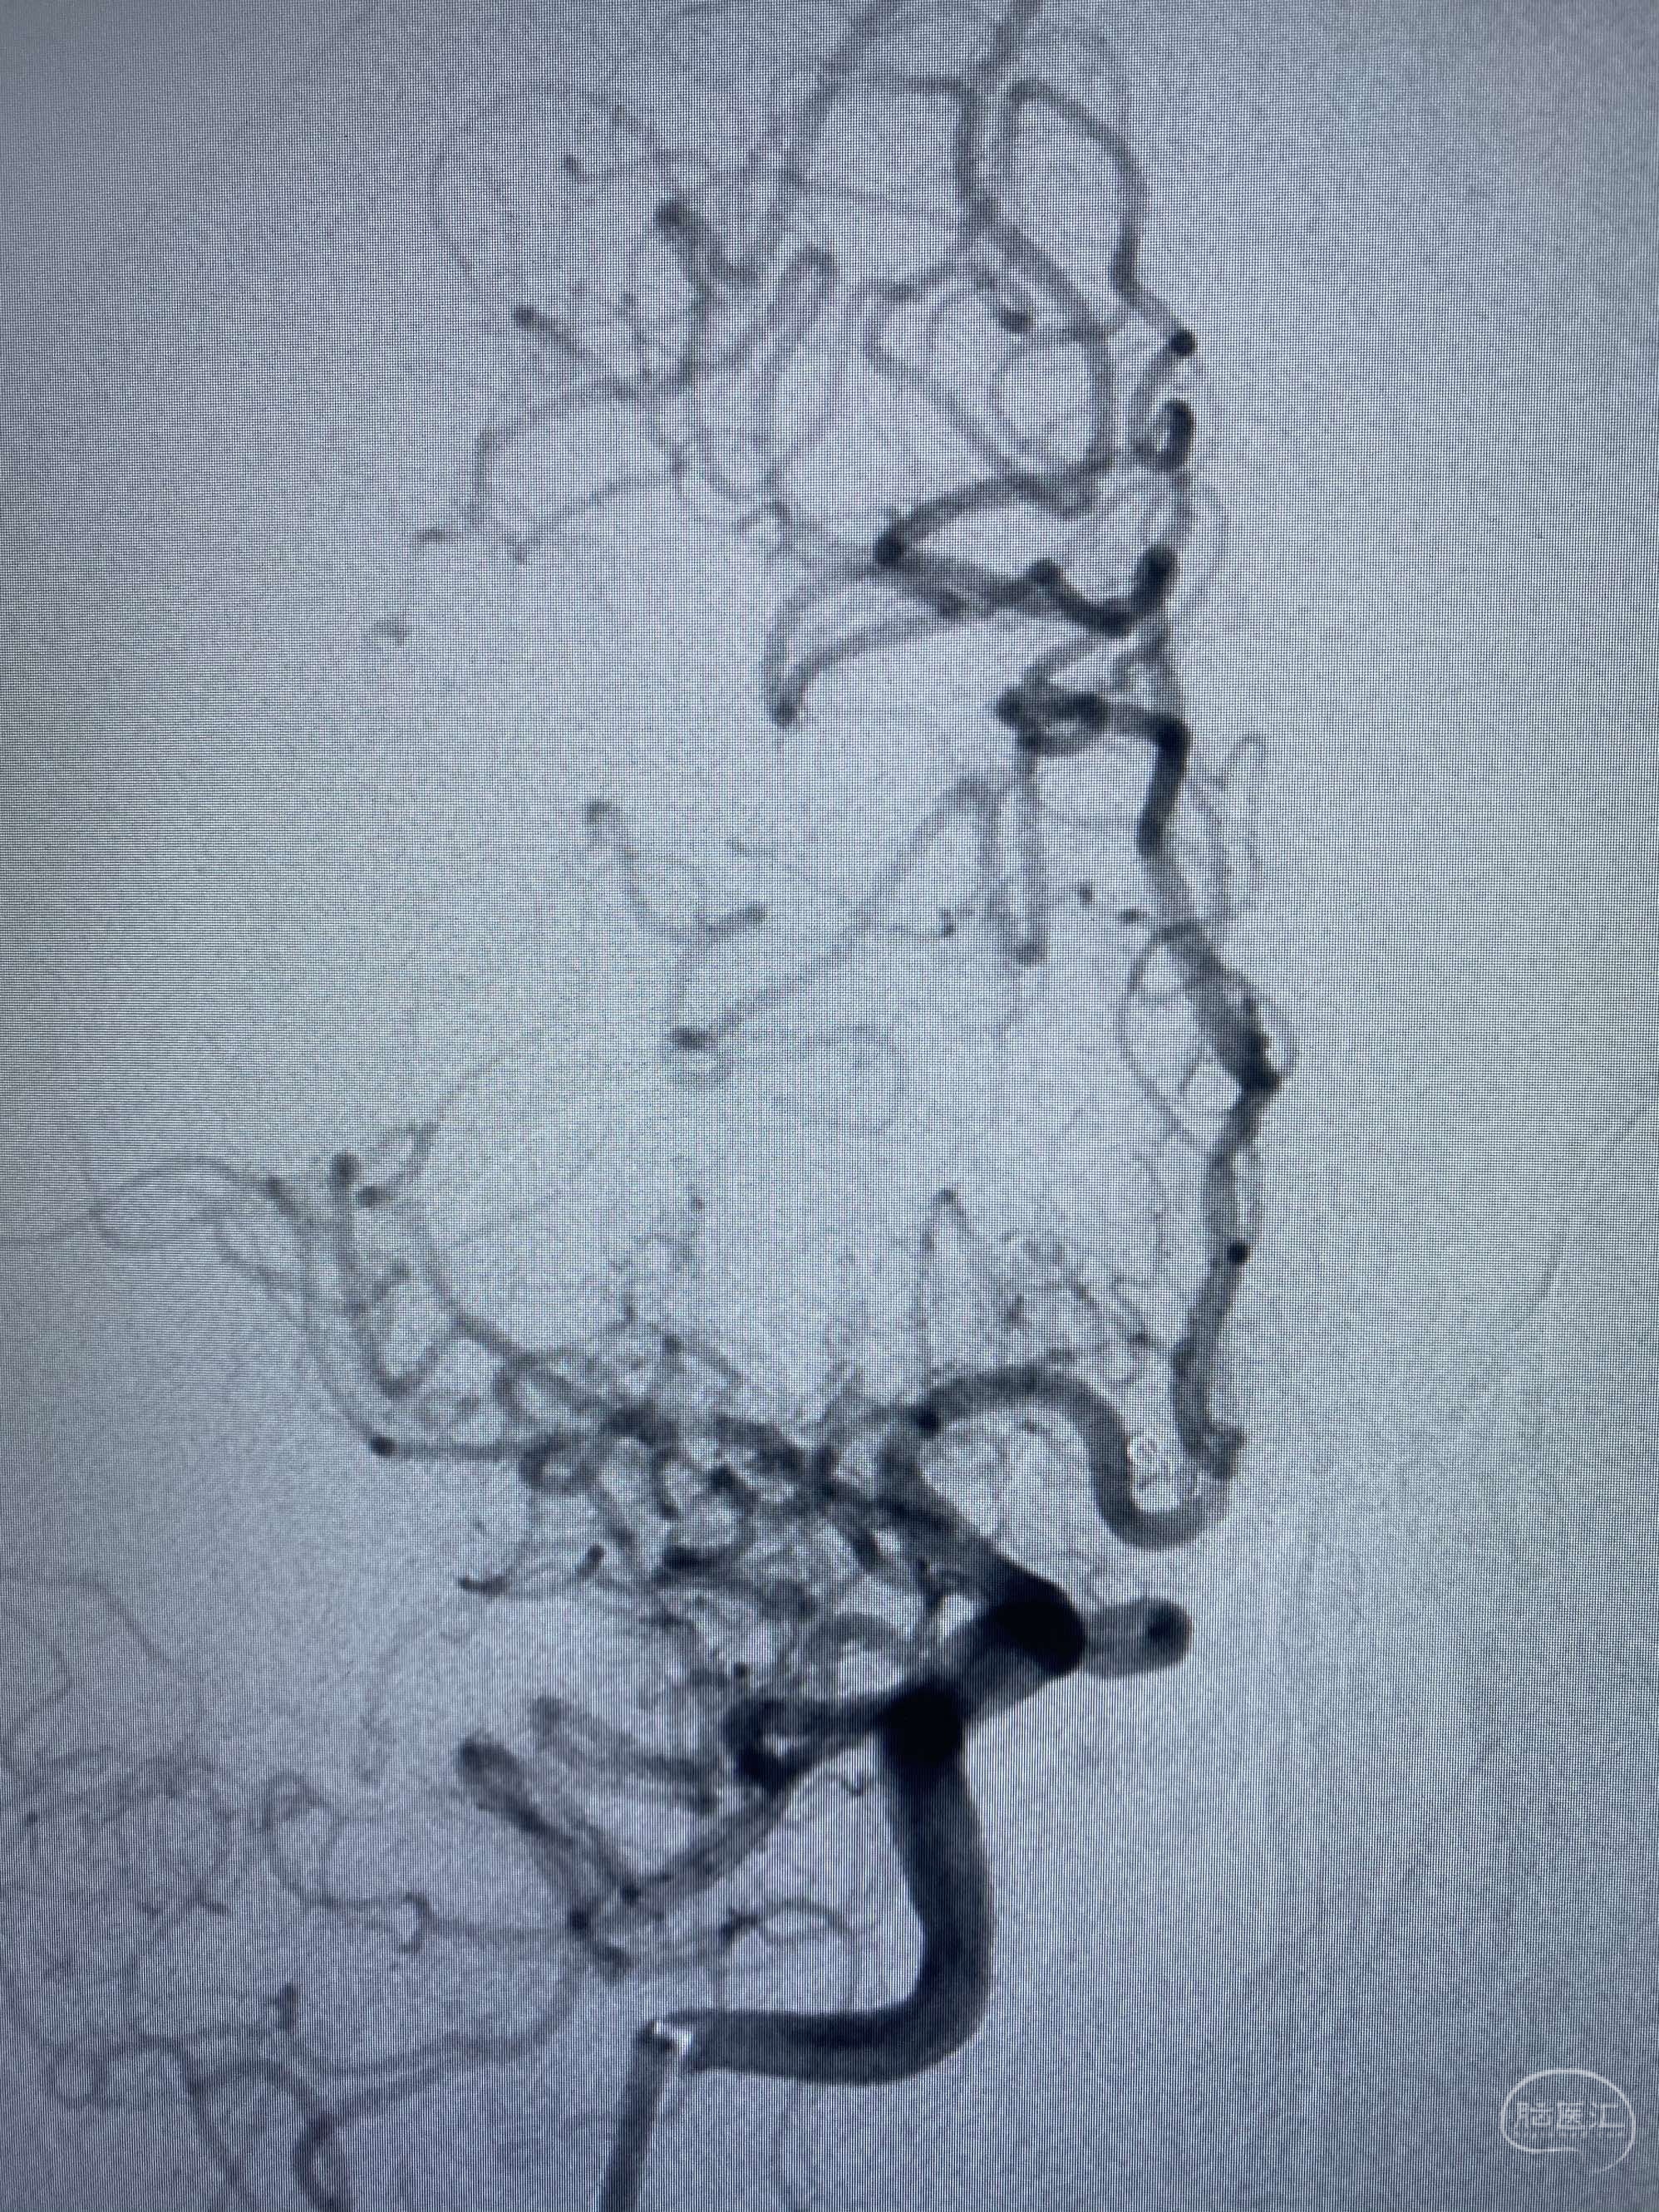

MLS,M79Y,sah,双侧MCA烟雾病,Heubner返动脉瘤,前交通段开窗,细支发出Heubner返动脉,瘤颈细长,瘤颈口比微导管细,弹簧圈2mmx3cm“隔山打牛”填塞治愈,Heubner返动脉保留。

Heubner返动脉是由大脑前动脉A1末端发出的豆纹动脉,由于走形和A1段相反,故称Heubner返动脉,该动脉梗塞可能引起尾状核头梗塞,引起偏瘫和面瘫,便身震颤等症状。